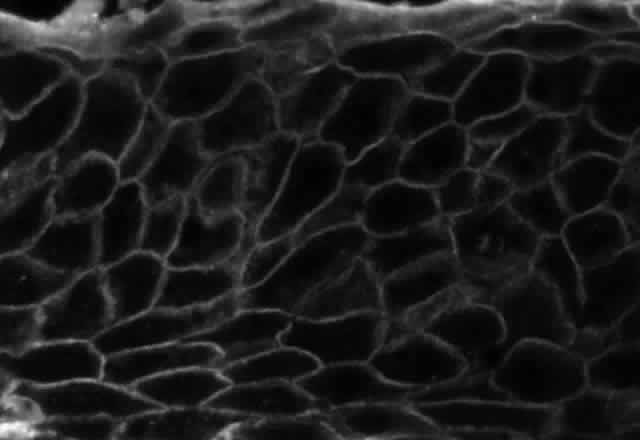

Pemphigus can be differentiated from bullous pemphigoid and from cicatricial pemphigoid on histologic and immunologic bases. Whereas the bullae in pemphigus are intraepidermal, those occurring in bullous pemphigoid and in cicatricial pemphigoid are subepidermal, between epidermis and dermis, or between mucosa and submucosa. Acantholysis is not present in the latter two conditions.5 In bullous pemphigoid and in cicatricial pemphigoid there are tissue-fixed immunoglobulins in the subepidermal basement membrane zone (Fig. 2).11 This is in contrast to the interepidermal fixation of antibodies (Fig. 3) seen in pemphigus (Table 1).

Fig. 2. Fluorescence microscopy of conjunctiva from a patient with cicatricial pemphigoid affecting the eye. The antibody used was a fluorescein-conjugated antibody directed against human IgG. Note the bright, continuous, linear deposition of IgG at the epithelial basement membrane zone, a finding virtually diagnostic of cicatricial pemphigoid.

Fig. 3. Immunofluorescence microscopy of conjunctiva from a patient with pemphigus vulgaris. The antibody is a fluorescein-conjugated antibody directed against human IgG. Note the bright staining of the intercellular cement, brightly outlining the borders of all of the epithelial cells.